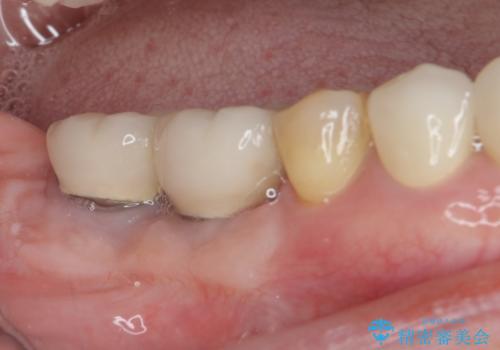

まずはクラウンを仮歯に替え、上顎の小臼歯2本を抜歯して矯正治療を実施し、その後歯周外科処置を行った上でオールセラミッククラウンにて補綴することとしました。

矯正治療は2年数ヶ月で終了したのですが、その後引っ越しをされ、クラウン装着までに長い期間がかかってしまいました。

矯正治療により長年気になっていた出っ歯が改善され、更には歯磨きの度に悩まされていた前歯の出血もなくなり、患者様には大変満足していただきました。